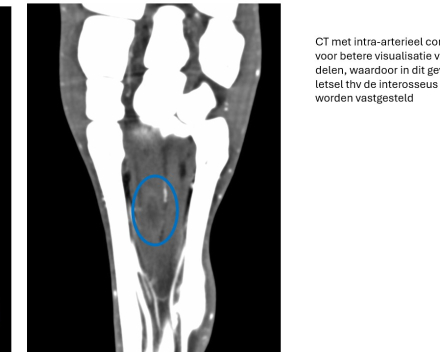

Dia 4 > La tomodensitométrie avec contraste intra-artériel permet une meilleure visualisation des tissus mous, ce qui a permis dans ce cas de détecter une lésion au niveau du tendon interosseux.